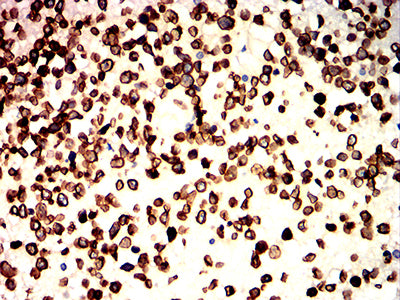

Immunohistochemical analysis of paraffin-embedded human brain tumors tissues using LMNB1 mouse mAb with DAB staining.